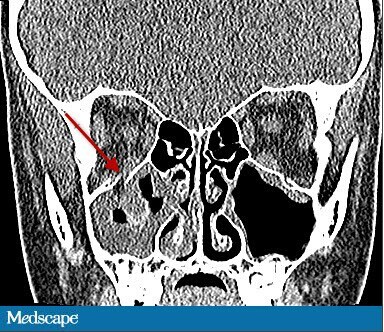

患者近视力 1.0,无视野缺损。第一眼位如图 1 所示。右眼上视有 -4 的眼球上转不足(图 2),下视有 -2 的下转不足。左眼运动正常。双眼水平运动正常。右眼第一眼位时眼压为 13mmHg,上视时眼压增加至 23mmHg。左眼眼压为 12 mmHg。瞳孔正常,双眼附属器以及前后节正常。眼球无震颤。颌面部 CT(图 3)显示右眼眶底轻微骨折。

图 3:颌面部 CT

根据检查结果,诊断为眼眶活板门样骨折致下直肌嵌顿。儿童尤其容易发生此型骨折。儿童骨质相对具有弹性,骨折后会产生反弹,使覆盖于上方的肌肉或者相邻的组织嵌入骨折缝(图 3)。这种肌肉嵌顿可以导致特征性的眼球运动障碍。本例患者恶心呕吐的症状提示眼心反射的可能性。

轴向或冠状扫描可发现该种骨折。然而一项回顾性研究发现,对于儿童来说,CT 检查只能发现少于 50% 此种骨折,大多数在外科手术过程中确诊。因此,诊断该种疾病应首先考虑临床症状,而非 CT 检查。